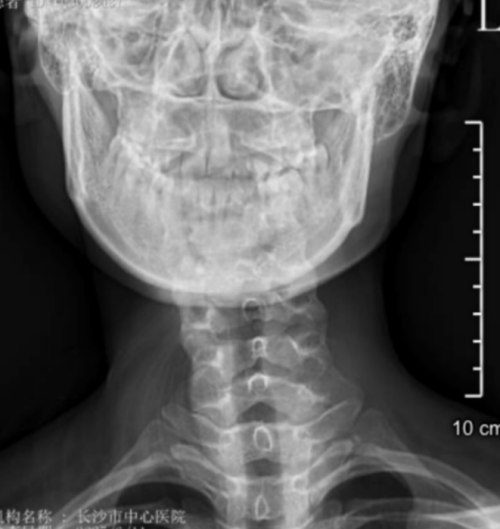

“患者属于典型的先天性肌性斜颈,由于延误治疗,颈部肌肉已形成纤维化改变。”该院脊柱外科二区主任、副主任医师曾浩介绍。面对这个特殊病例,医疗团队决定采用先进的微创技术——通过仅3厘米的切口,在放大数倍的手术视野下,精准松解挛缩的胸锁乳突肌,同时保护重要的神经血管。

李琳出生后没多久,细心的父母就发现女儿的脖子总是向右倾斜,起初以为是睡姿问题,可随着年岁增长,这个“小毛病”不仅没有消失,反而带来了更多困扰:颈椎逐渐变形、肩背持续疼痛,连最简单的转头动作都变得困难。